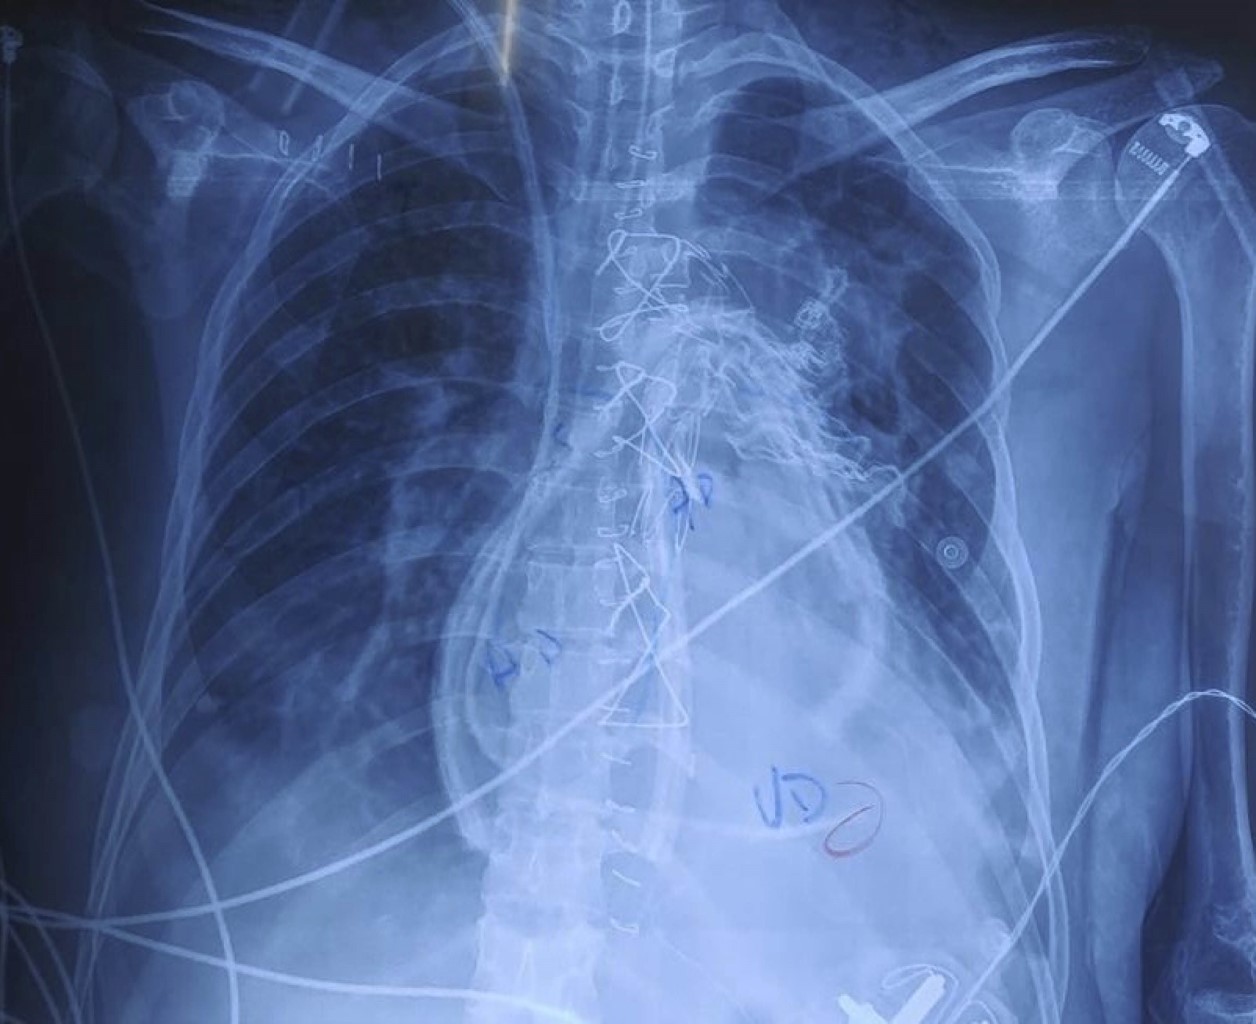

A first transthoracic echocardiogram was performed with generalized dilatation in the four chambers, decreased contractile dynamics, vena cava with diameters of 21 mm, distensibility of 33%. Subsequently, upon admission to our hospital unit in charge of cardiology, a second transthoracic echocardiogram was performed. Cardiomyopathy in dilated phase of undetermined origin, left ventricular systolic dysfunction with left ventricular ejection fraction of 43%, with abnormal global and segmental contractility due to global hypokinesia. Severe dilatation of the right chambers. Moderate mitral and tricuspid insufficiency, mild aortic insufficiency and severe pulmonary insufficiency. Severe pulmonary arterial hypertension due to pulmonary artery systolic pressure of 100 mmHg. Diagnostic cardiac catheterization was performed by interventional cardiology with the results of severe pulmonary arterial hypertension unresponsive to oxygen challenge, and an aortogram with anatomy compatible with common arterial trunk type I was performed (Figure 1). Angiotomography with reconstruction of large vessels was performed, where the interruption distal to the subclavian artery and an aneurysmal dilatation were identified (Figure 2). It was decided to evaluate the patient by the cardiac surgery service.

Figure 1